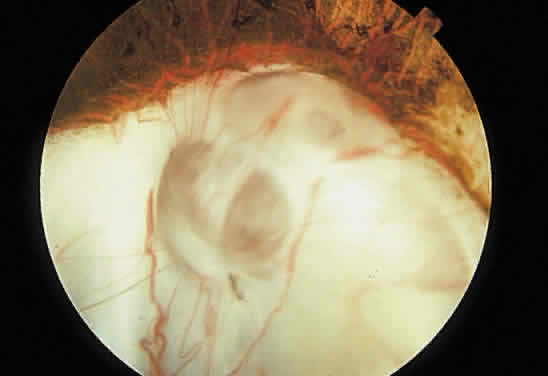

Retinochoroidal colobomas are glistening white or yellow defects with distinct borders that occur inferior or inferonasal to the optic disc (Fig. 12). They may extend up to and involve the optic disc (Fig. 13), or they may be seen as isolated chorioretinal defects. The margins of the coloboma often are pigmented, and the defect is filled with abnormal retinal tissue. Anteriorly, the defect can extend as far as the iris and produce an inferonasal gap (Fig. 14). These anomalies may occur in otherwise normal persons or in association with chromosomal abnormalities or multisystem diseases, such as trisomy 13, the Aicardi syndrome, Goldenhar's syndrome, and the CHARGE association.148,152,153 Occasionally, autosomal dominant or recessive inheritance patterns are found, but often none are evident.152 In families with autosomal dominant inheritance, variable expression of the genetic trait makes genetic counseling difficult.154

Fig. 12. Isolated retinochoroidal coloboma with pigmented borders positioned inferior to the nerve head. The sclera is visible through the thinned, overlying retinal tissue.

Fig. 13. Retinochoroidal coloboma involving the optic disc and inferonasal fundus. The borders of the abnormality are nonpigmented, and the defect appears to be filled with fibroglial tissue.

Embryologically, retinochoroidal colobomas arise from failure of the embryonic fissure to close. Consequently, the inner and outer layers of the optic cup are abnormal in this region. The inner layer (sensory retina) usually is present as a membrane of undifferentiated retina that may have blood vessels going through it (see Figs. 12 and 13). The outer layer (RPE) is absent, and since the choroid is dependent on the RPE for its development, it also is lacking.